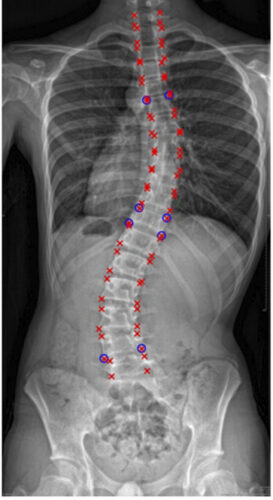

كيف يتم تشخيص اعوجاج العمود الفقري عند الأطفال المصابين بمتلازمة ريت؟

يتم التشخيص من خلال:

الفحص السريري: حيث يراقب الطبيب استقامة الظهر أثناء الوقوف أو الجلوس.

اختبار الانحناء للأمام: للكشف عن أي بروز أو انحناء غير طبيعي.

الأشعة السينية (X-ray): لتحديد زاوية كوب (Cobb Angle) التي تُستخدم لتقييم شدة الاعوجاج بدقة.